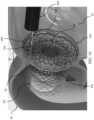

FIG.1 is a cross-sectional view of a portion of the digestive tract in a human body with a gastrointestinal device positioned in the pylorus, according to some embodiments;

FIG.1 shows a cross-sectional view of a portion of a humandigestive tract10, showing astomach16,intestine18, thepylorus20, and theduodenum22. The pylorus generally includes thepyloric antrum24 and thepyloric sphincter26. As shown inFIG.1, agastrointestinal device100 may be positioned between thestomach16 and theintestine18. In some examples, thegastrointestinal device100 is positioned within the pylorus20 such that one or more portions of thegastrointestinal device100 are positioned within or adjacent to thepyloric antrum24. In some examples, thegastrointestinal device100 is additionally or alternatively positioned with one or more portions of thegastrointestinal device100 positioned within theduodenum22.